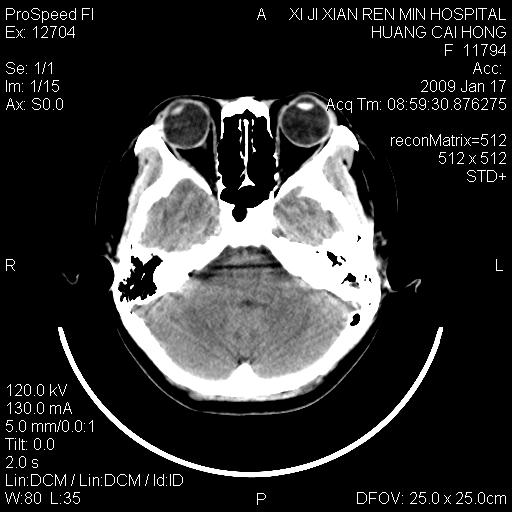

以下是引用zbp537在2009-1-19 13:54:00的发言:[br]首先考虑脑炎。[br]诊断依据:[br]1、患者较年轻。[br]2、有感冒病史。[br]3、左侧颞枕叶这么大一片低密度影,占位征象却不明显,不符合肿瘤特征,其内的高密度影为出血灶。

以下是引用xiaoniu在2009-1-19 13:29:00的发言:[br]左侧颞叶三角形低密度影,占位效应不明显,其内点片样高密都影,青少年患者,首先考虑:少突胶质瘤。因为有感冒病史,不能除外感染的可能。